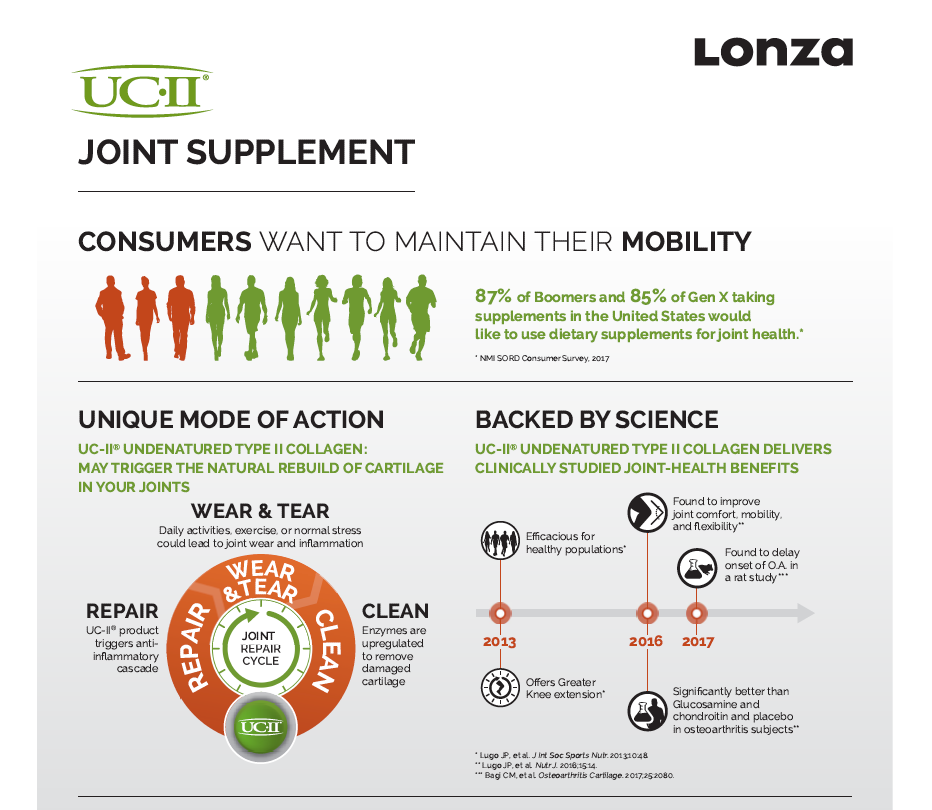

A patented Type II Collagen, sourced from chicken cartilage from USA.

- Rebuild and reduce cartilage & Joint Fluid Loss

- Relieve Pain & Restores joint flexibility

- Proven to be 2x more effective than glucosamine + chondroitin

A premium natural extract from eggshell membrane developed in Spain. Contains over 500 active compounds, including collagen, hyaluronic acid, glucosamine, and chondroitin.

- Reduces joint inflammation naturally

- Rebuild, replanish damaged cartilage & Fluid

- Relieves knee pain in 7 days